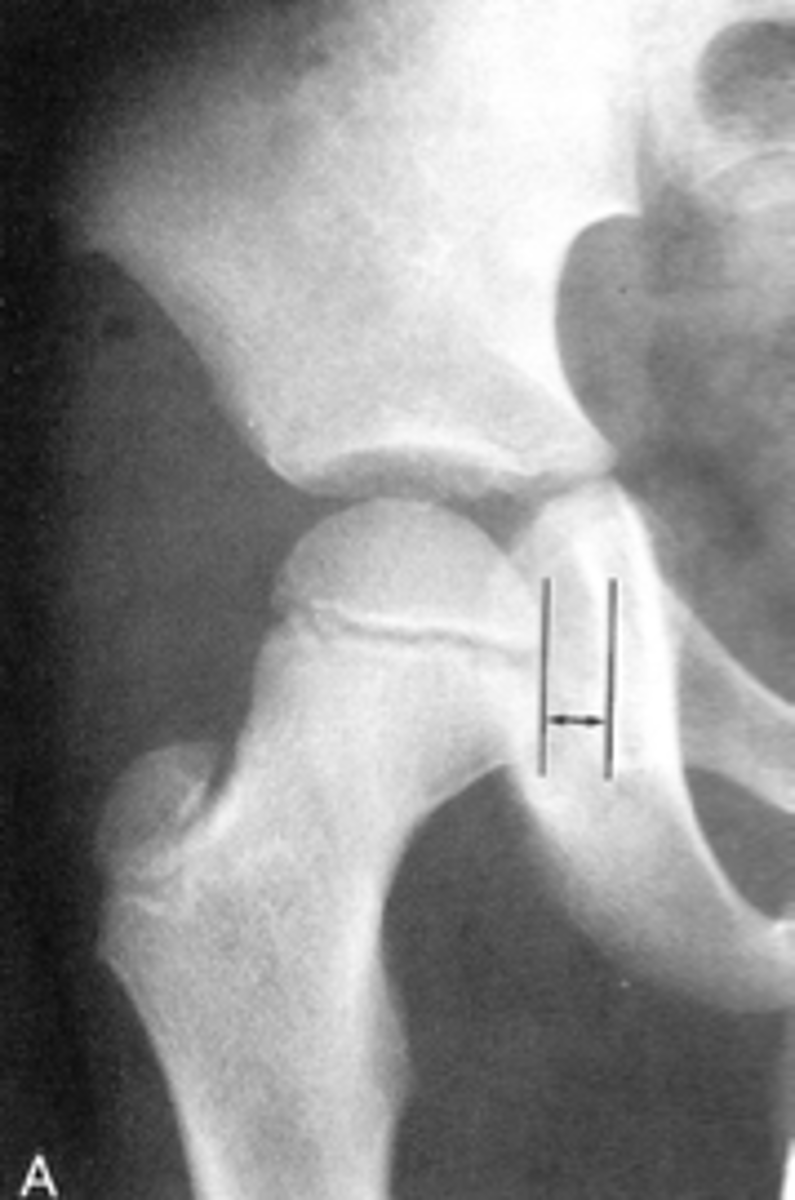

Kohler's teardrop distance

ID measurement line

<p>ID measurement line</p>

- AP pelvis

- AP hip

What views are needed to see Kohler's teardrop distance?

<p>What views are needed to see Kohler's teardrop distance?</p>

- Medial margin of femoral head

- Lateral border of teardrop

Kohler's teardrop distance landmarks

<p>Kohler's teardrop distance landmarks</p>

6-11 mm

Normal Kohler's teardrop distance measurement

<p>Normal Kohler's teardrop distance measurement</p>

2 mm

The normal Kohler's teardrop distance is 6-11 mm, and there should be no greater than a _____ difference when comparing to the contralateral side

<p>The normal Kohler's teardrop distance is 6-11 mm, and there should be no greater than a _____ difference when comparing to the contralateral side</p>

Hip joint effusion

Clinical significance of an enlarged Kohler's teardrop distance

<p>Clinical significance of an enlarged Kohler's teardrop distance</p>

Waldenstrom's sign

What sign indicates an enlarged Kohler's teardrop distance?

- Accentutation of the normal limits

<p>What sign indicates an enlarged Kohler's teardrop distance?</p><p>- Accentutation of the normal limits</p>

Intracapsular swelling/joint effusion

Waldenstrom's sign is usually an indication of _____

<p>Waldenstrom's sign is usually an indication of _____</p>

Inflammatory arthritis

Clinical significance of a small Kohler's teardrop distance

<p>Clinical significance of a small Kohler's teardrop distance</p>